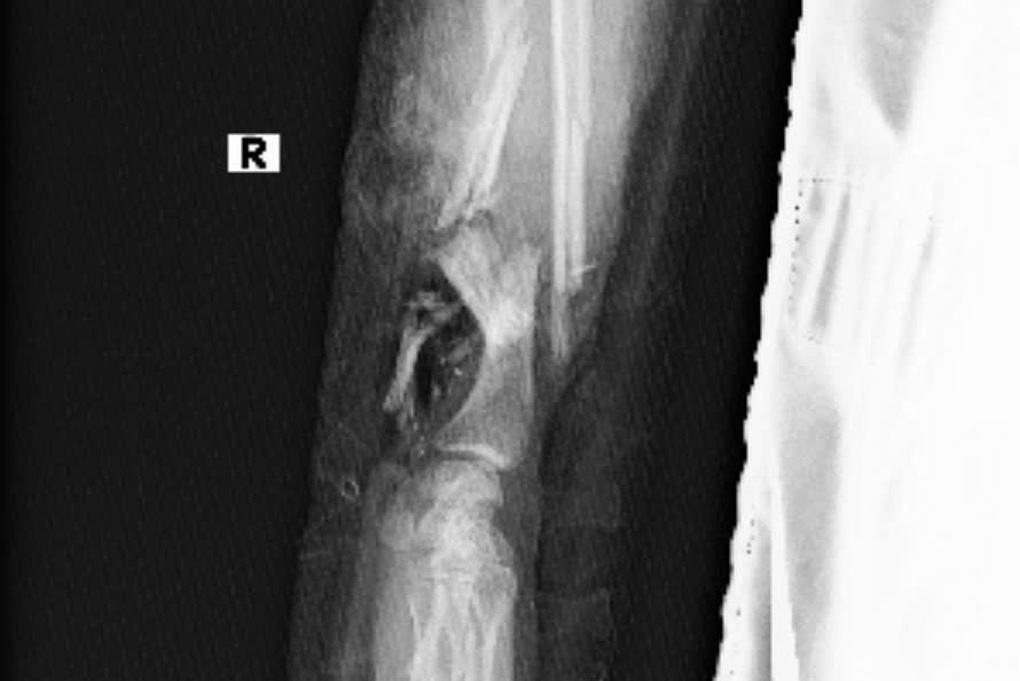

Trao đổi với phóng viên Dân trí ngày 25/9, thành viên ê-kíp thực hiện ca phẫu thuật nêu trên cho biết, thời điểm nhập viện, bệnh nhân bị dập nát 1/3 dưới cẳng tay và đứt lìa bàn tay phải sau tai nạn lao động.

Tai nạn khiến vùng tay của cô gái bị dập nát, đứt lìa (Ảnh: BV)

Với tình trạng dập nát mạch máu và các mô rất bẩn, nếu nối lại ngay lập tức thì chi của bệnh nhân sau đó sẽ bị ngắn, và sau đó vị trí nối sẽ tiếp tục hoại tử, khiến ca ghép nối sẽ thất bại. Ngoài ra, bệnh nhân có nguy cơ nhiễm trùng sau mổ, gây biến chứng nhiễm trùng huyết, suy đa tạng, thậm chí mất cả mẹ lẫn con.